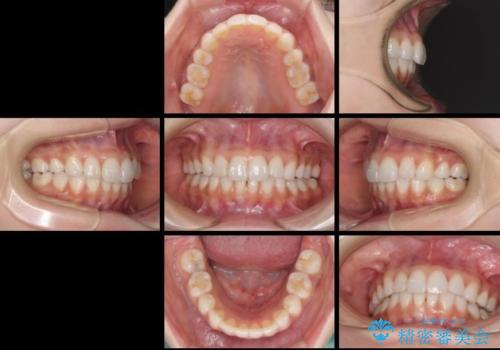

矯正治療の後戻り インビザラインによる再矯正治療

デコボコが解消されるのはもちろんのこと、突出感のあった前歯を引っ込めることができ、患者様には大変満足していただきました。

- 1年2ヶ月